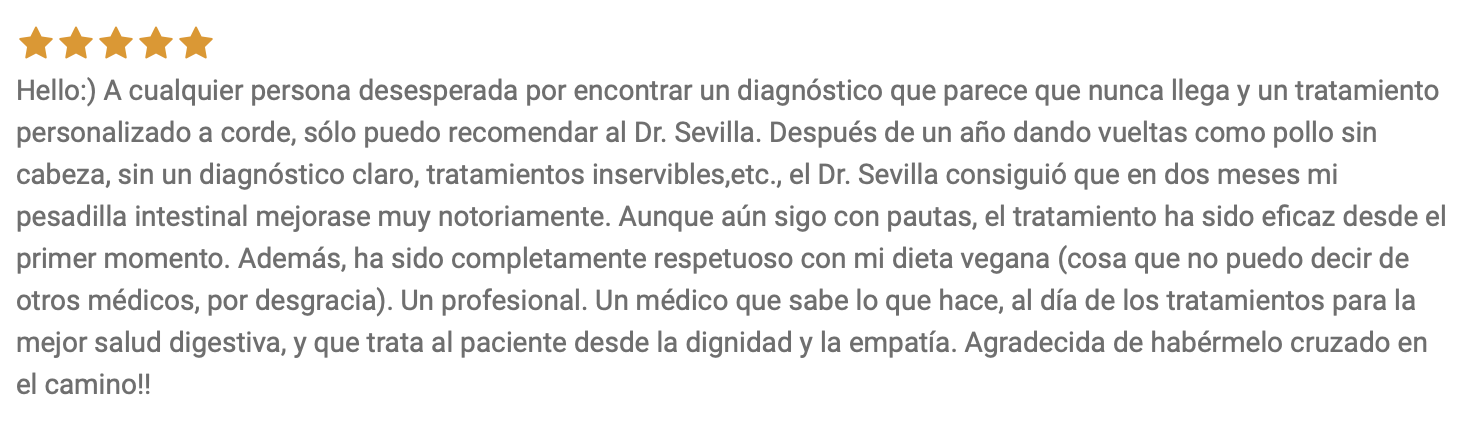

OPINIONES EN TOPDOCTORS.ES (TOP DOCTORS ESPAÑA)

Accede a la lógica clínica que cambiará la forma de entender y abordar tus síntomas

Hoy puedes acceder a esta formación médica por mucho menos de lo que te costaría una consulta privada de digestivo o seguir probando suplementos y cambios en tu dieta al azar esperando que alguno funcione sin saber realmente el motivo.